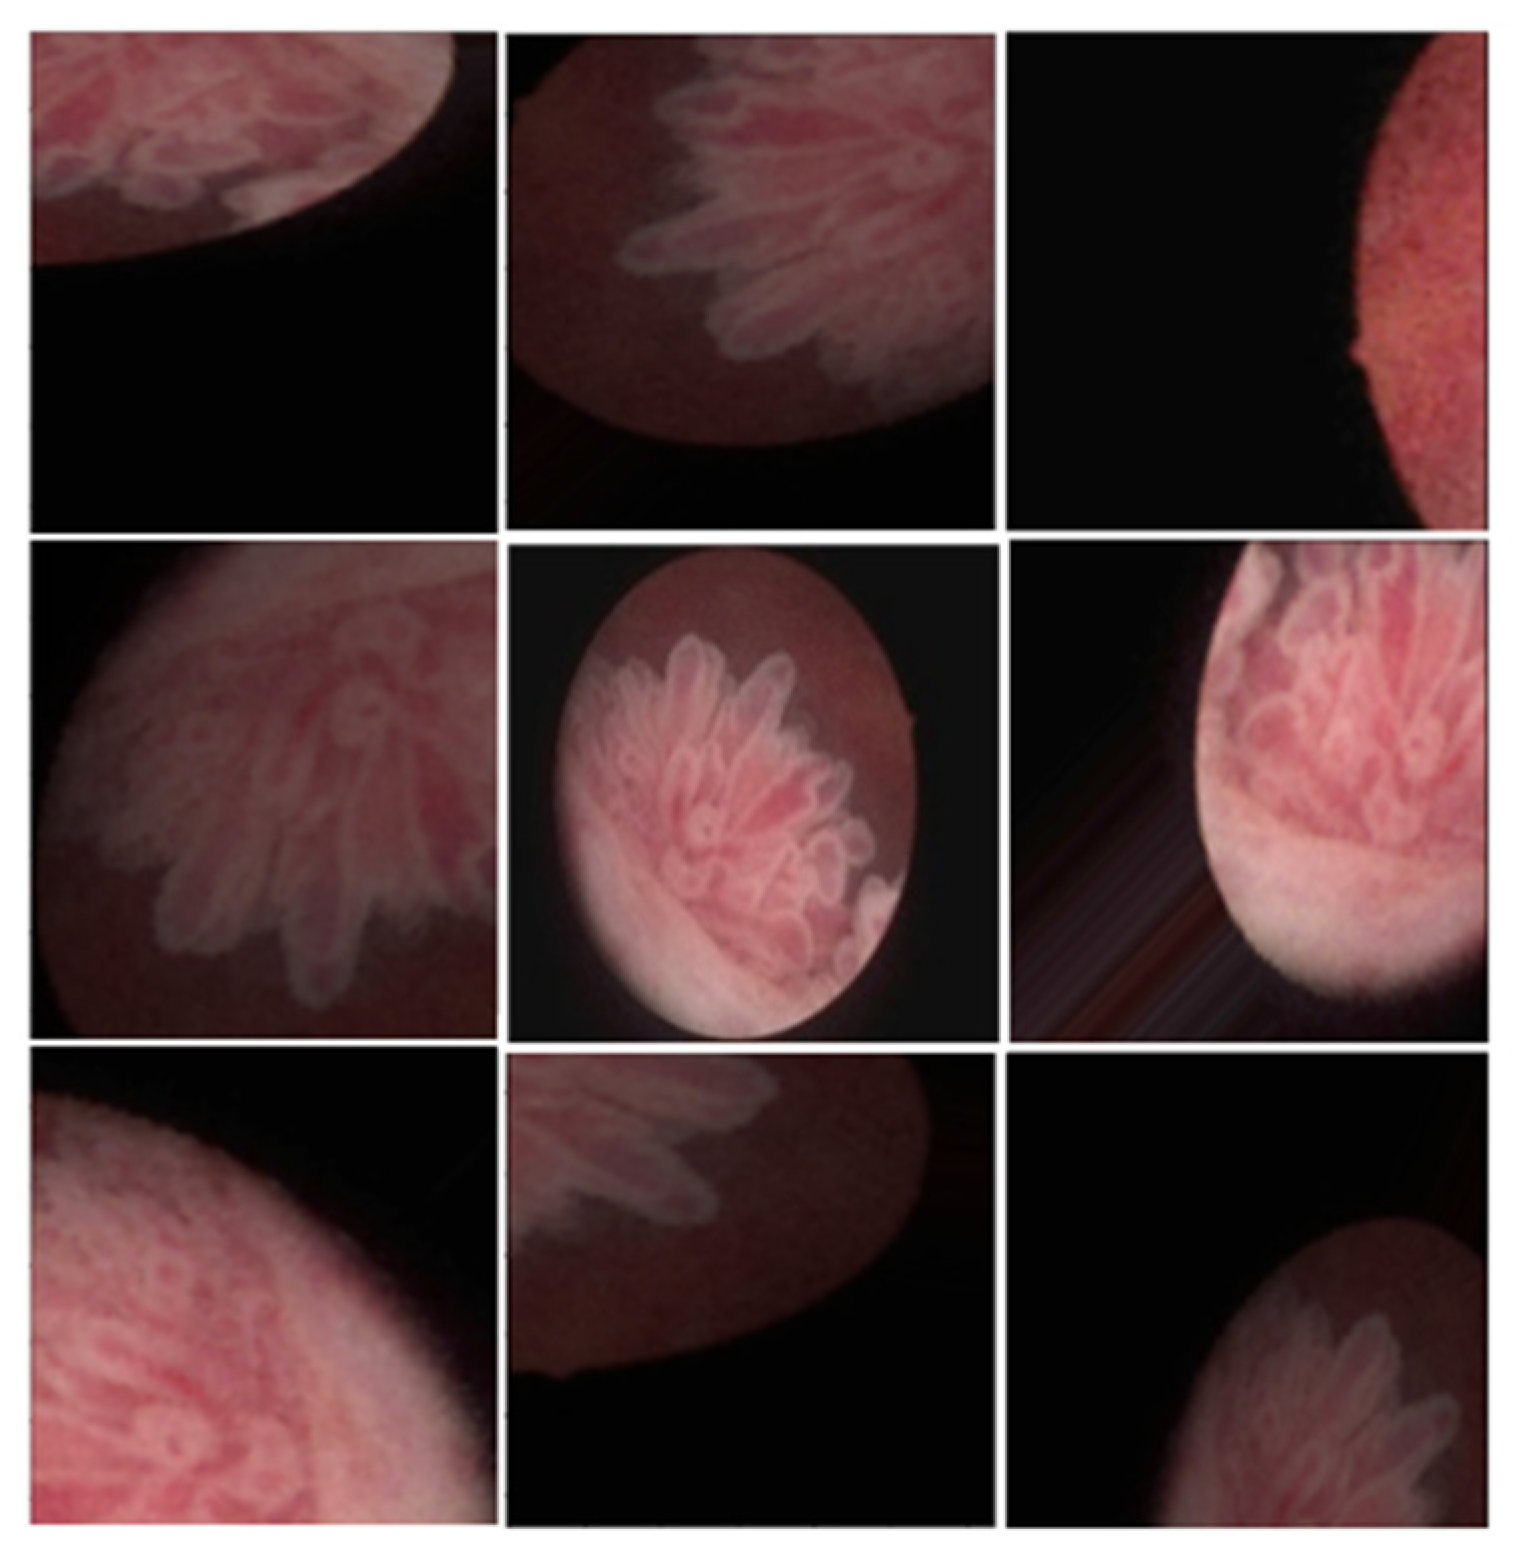

Figure 1.

Sample original endoscopy images and segmentation mask of the bladder cancer.

This study utilized data from 772 patients. Each patient’s cystoscope images were annotated with corresponding biopsy results (normal, Ta, T1, T2, and CIS) and morphology (normal, flat, papillary, and mixed). Table 1 presents the patients’ basic characteristics, as well as the distribution of image types and biopsy results. A total of 8,566 images from these 772 patients were used in this study. Experienced urologists labeled the bladder cancer areas and their corresponding pathological results (Figure 1).